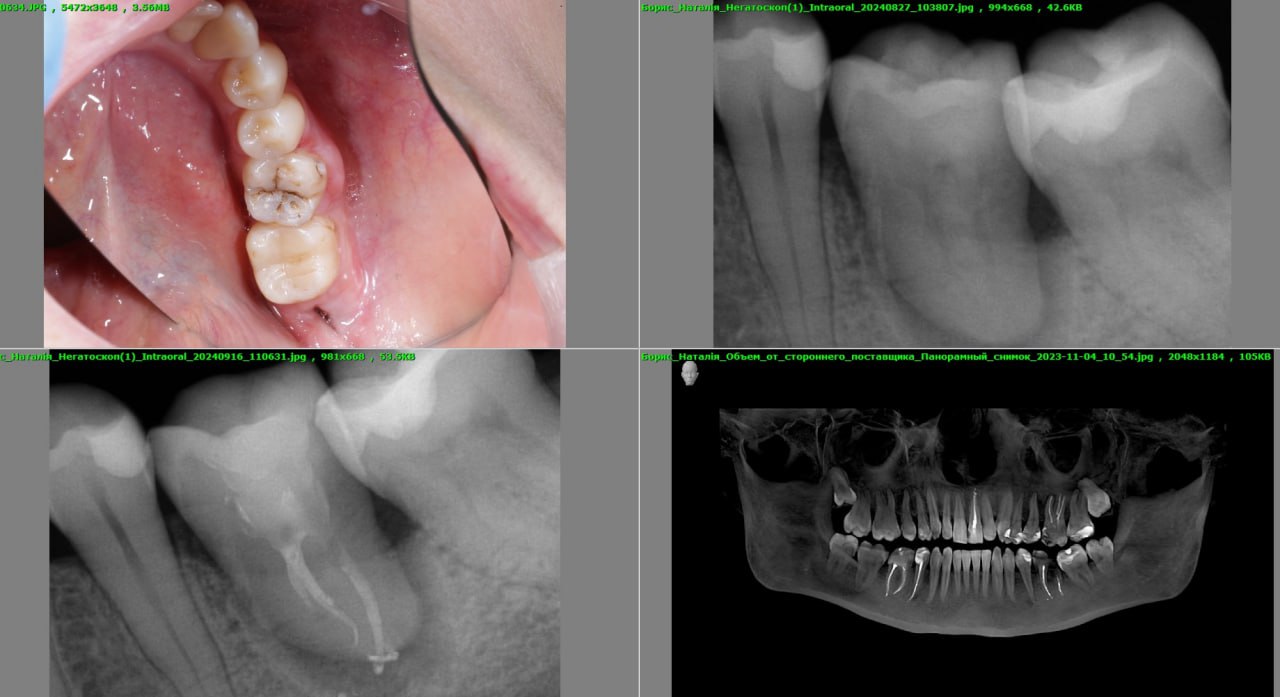

Клінічний кейс

Пацієнт, 35 років. Втратив 6-й зуб. Імплантацію не хотів.

Було проведено трансплантацію за один візит. Через 6 місяців — повне приживлення. Через 1,5 року — ідеальний результат.

"Я забув, який зуб пересаджували"